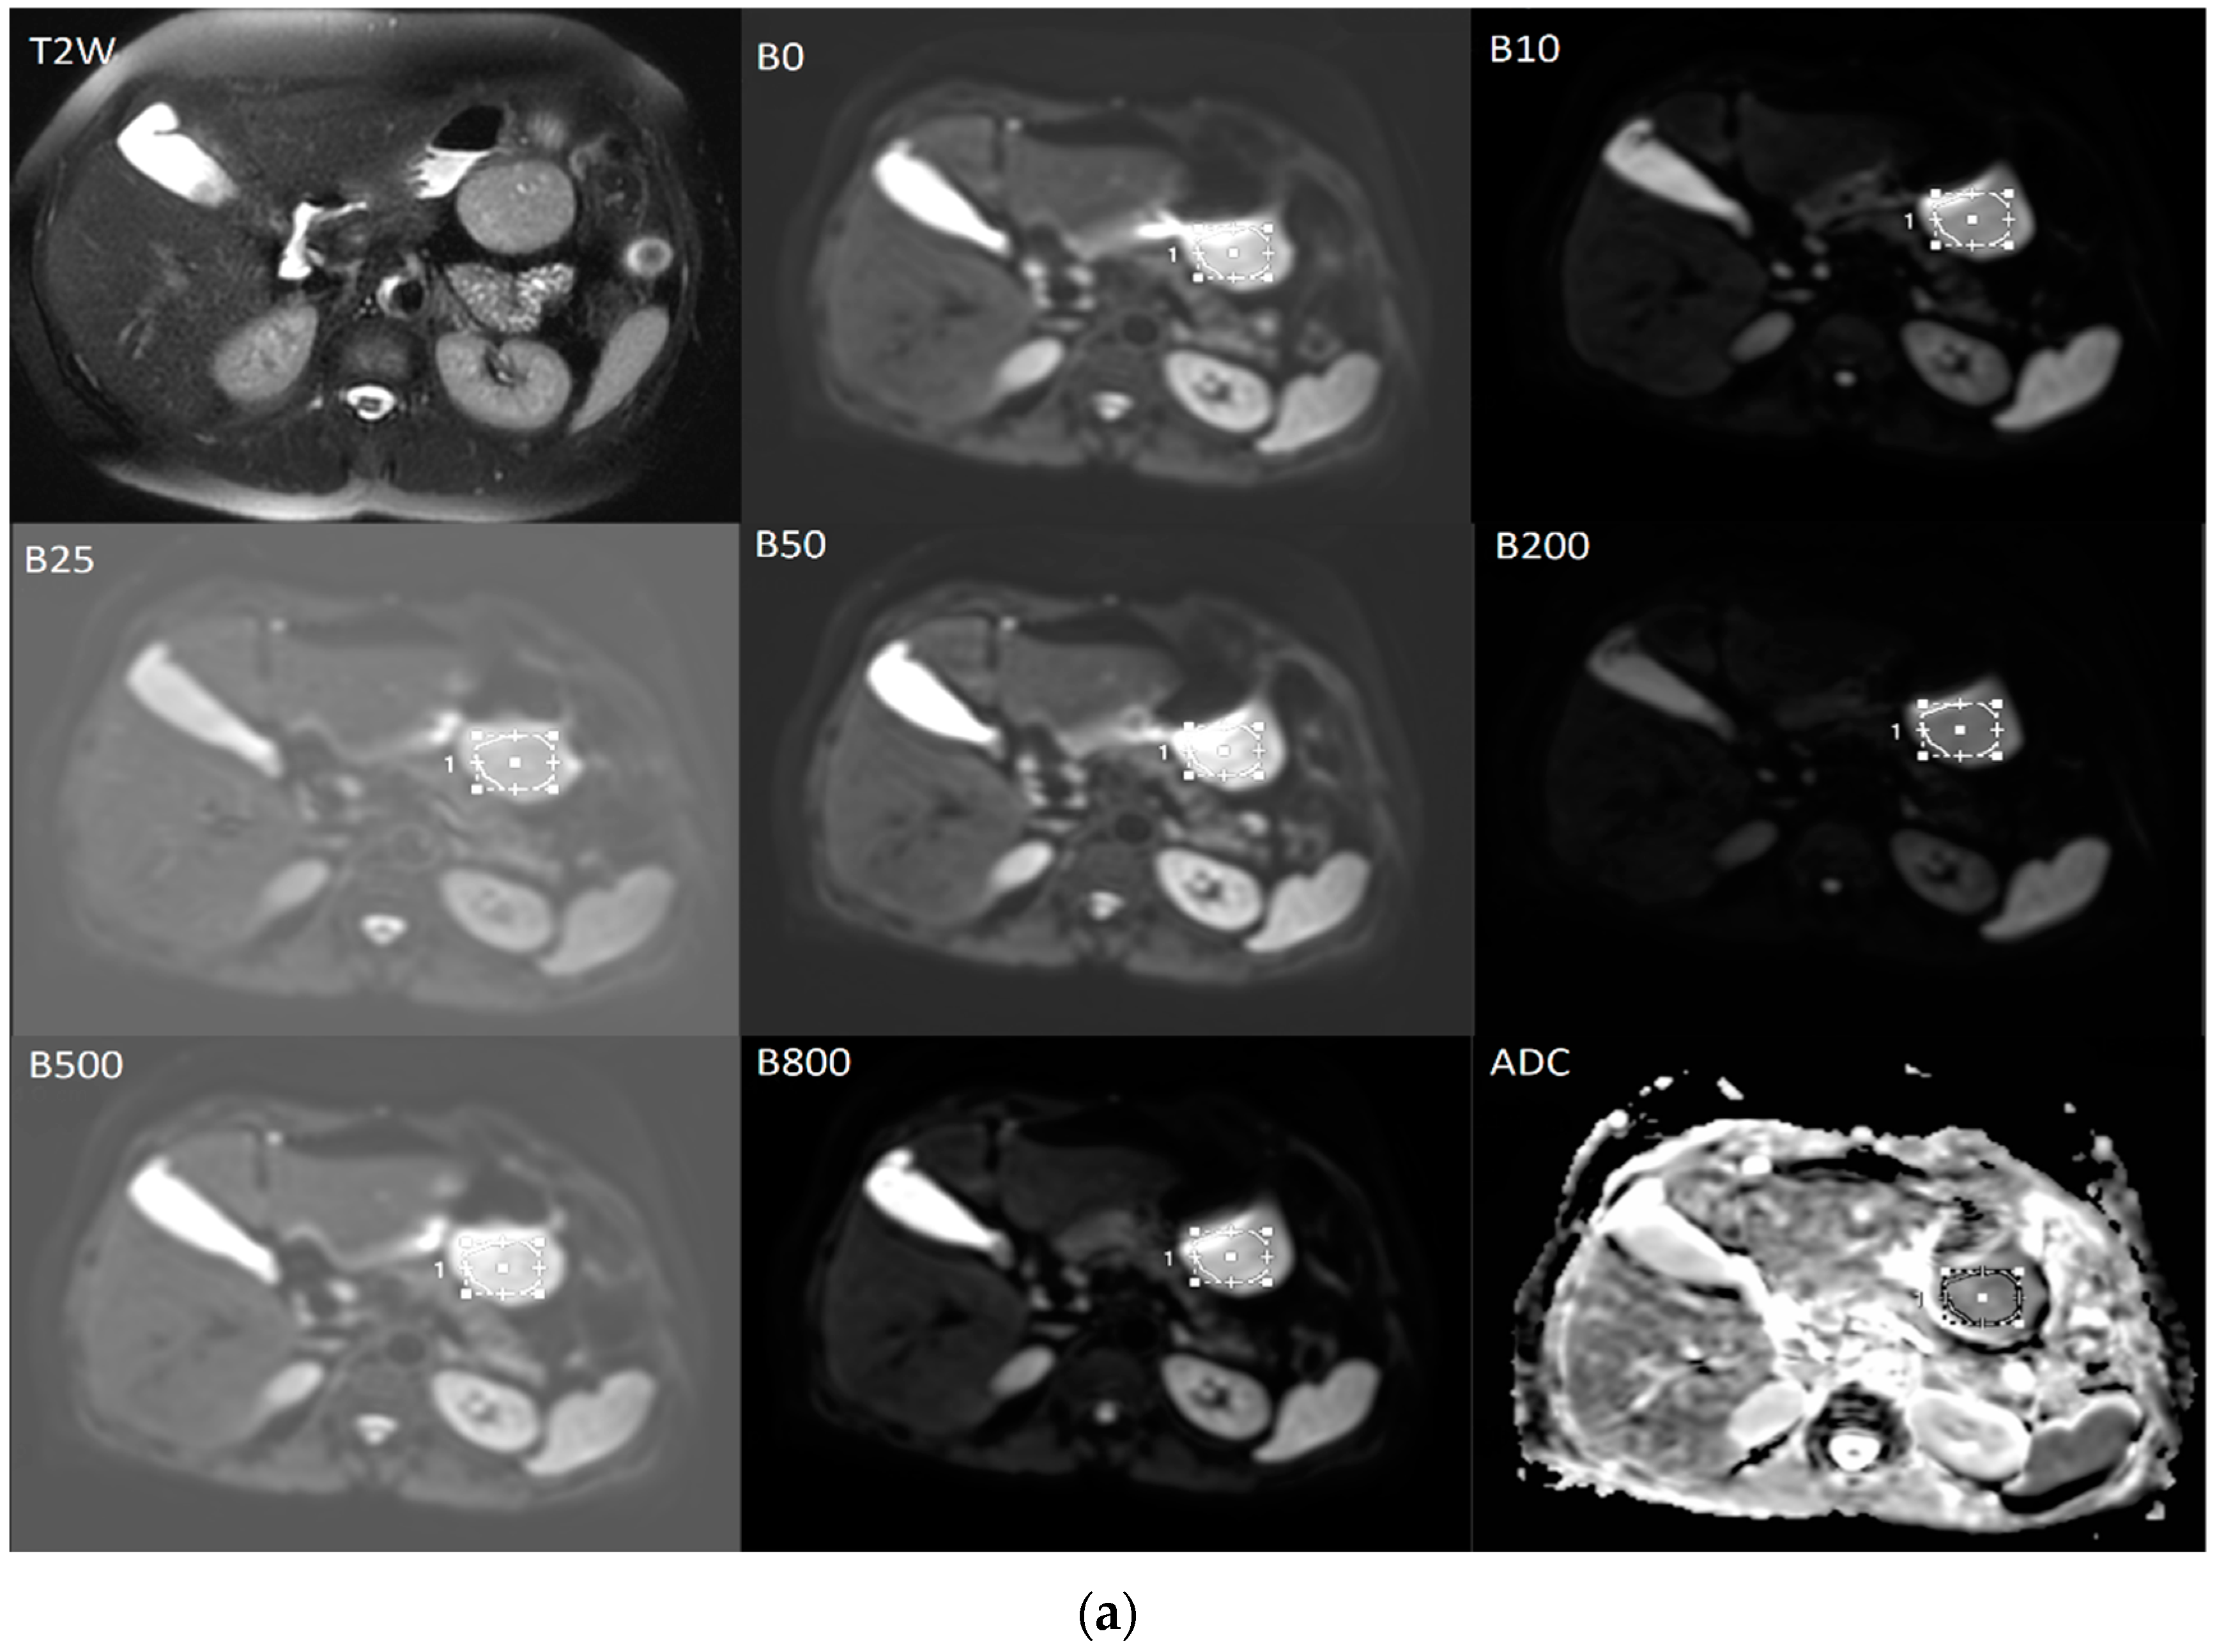

2.4. Processing of DWI Images and Calculation of ADC and IVIM Parameters

The diffusion weighted images were analyzed by a radiologist with 6 years of experience. T2-weighted images were used to help to determining the localization of the tumor more clearly and avoid necrotic areas (Figure 6). On diffusion-weighted images for b = 0, ROI were positioned within the solid tumor region, on three contiguous axial sections at the place of the largest tumor diameter and then automatically copied to all higher b-values parametric maps. Quantitative ADC maps were calculated on voxel-by-voxel basis on the commercial workstation by using the mono-exponential model for the combination of b = 0 and b = 800 [15].

Figure 6.

The averaged signal intensity decay and representative IVIM DW images. T2-weighted image in axial view is used for the precise localization of the tumor. DWI with multiple b-values and ROIs (a) followed by signal attenuation curve (b) where true diffusion coefficient (D slow), pseudo-diffusion coefficient (D fast) and perfusion fraction (f) were calculated based on the bi-exponential model.

The data for IVIM parameters: true diffusion coefficient (D slow), pseudo-diffusion coefficient (D fast), and perfusion fraction (f) were calculated based on the bi-exponential model by using the MITK Diffusion software, after fitting the signal values from manually located ROIs [15].

The final values of D slow, D fast, f, and the ADC for b = 0 and 800 s/mm² were calculated by averaging the three measurements (Figure 6) [15].